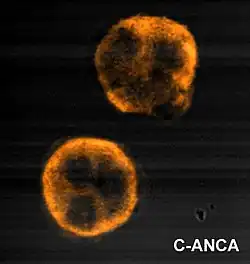

Antineutrophil cytoplasmic antibodies (ANCAs) now are widely presumed to be responsible for the inflammation in GPA.[12] The typical ANCAs in GPA are those that react with proteinase 3, an enzyme prevalent in neutrophil granulocytes.[7] In vitro studies have found that ANCAs can activate neutrophils, increase their adherence to endothelium, and induce their degranulation that can damage endothelial cells. This phenomenon could cause extensive damage to the vessel wall, especially to arterioles.[12]

Granulomatosis with polyangiitis is usually suspected only when a person has had unexplained symptoms for a long period. The determination of ANCAs can aid in diagnosing GPA, but positivity is not conclusive, and negative ANCAs are insufficient to reject the diagnosis. More than 90% of people who have GPA test positive for ANCAs.[19] Cytoplasmic-staining ANCAs that react with the enzyme proteinase 3 (cANCA) in neutrophils (a type of white blood cells) are associated with GPA.[12] Involvement of the ears, nose, and throat is more common in granulomatosis with polyangiitis than in the similar condition microscopic polyangiitis.[7]